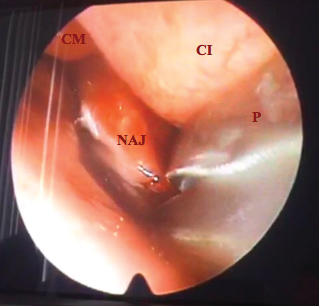

Se realizó biopsia por medio de nasofibrolaringoscopia previa a infiltración con lidocaína, se toman dos muestras de lesión en coana izquierda sin sangrado significativo (Figura 5)

.

Figura 5. NAJ[Nasoangiofibroma Juvenil], CI[Cornete inferior], CM [Cornete Medio], P [Pinza de Biopsia]. Fuente: Hospital Militar Central de Bogotá.